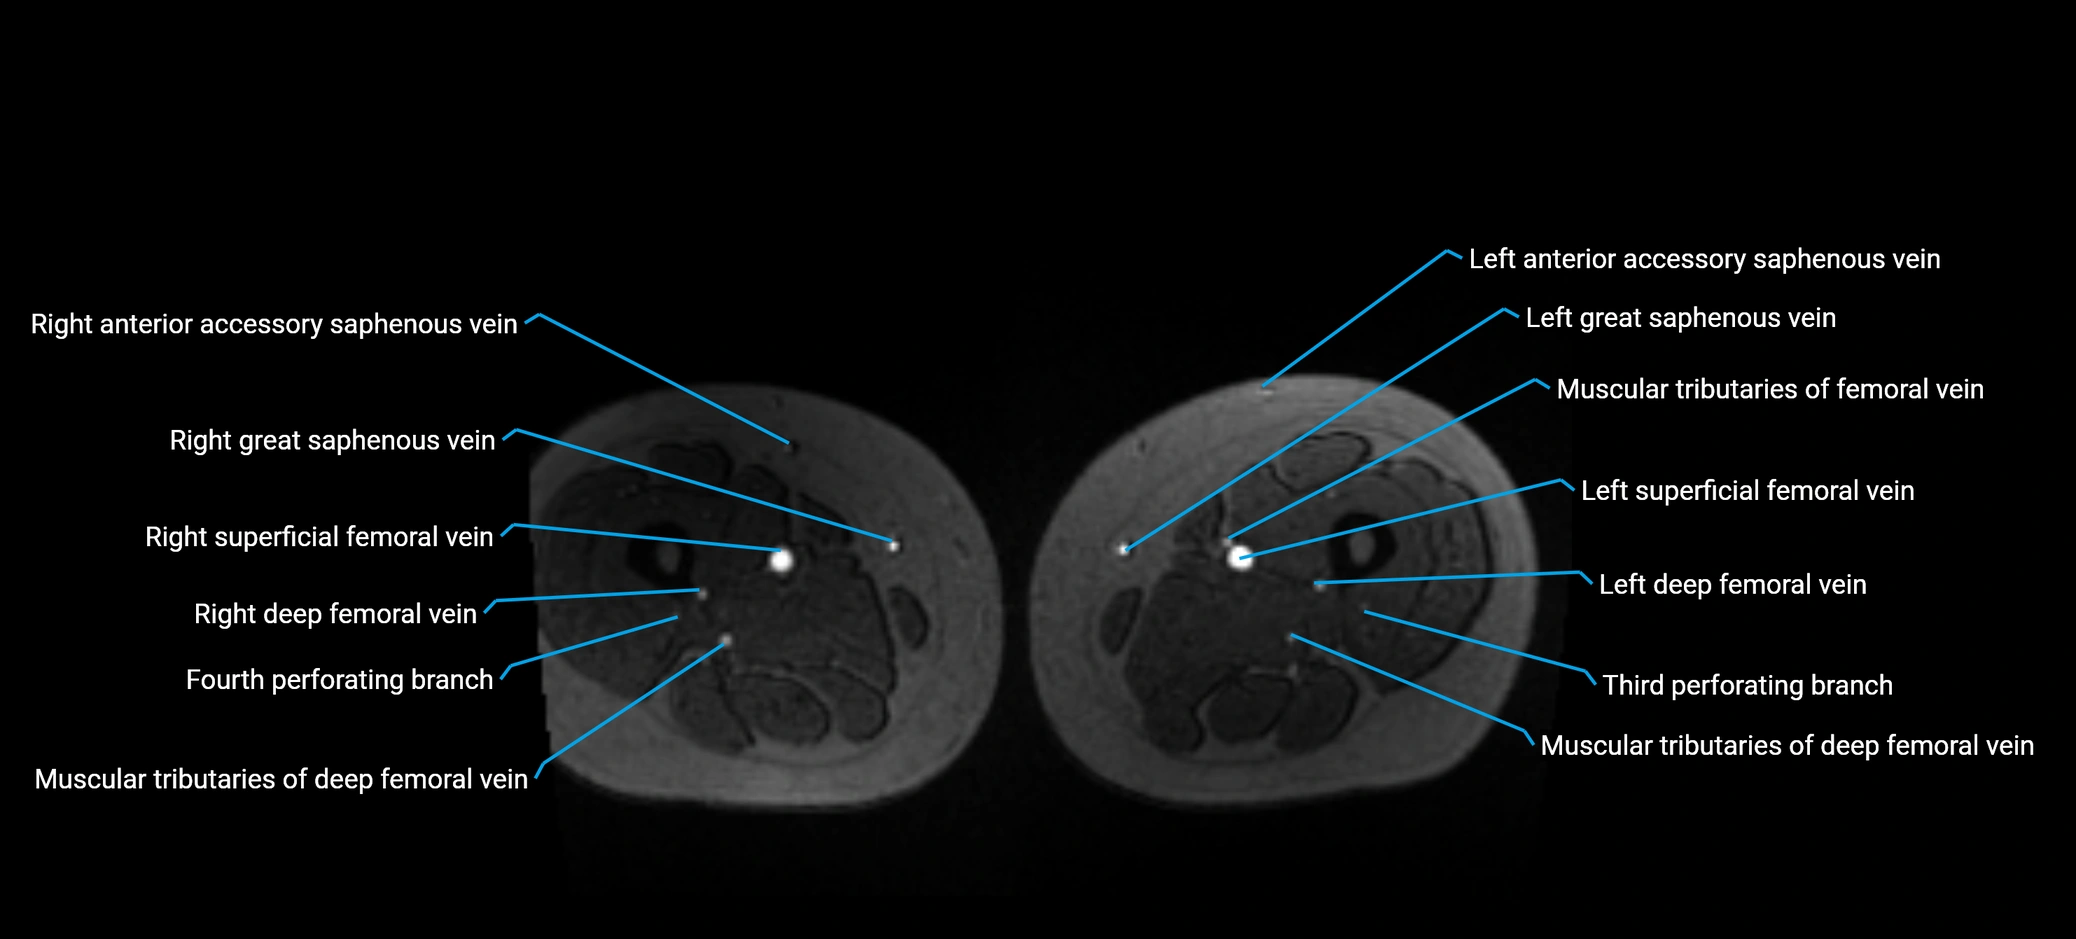

MRI image

image